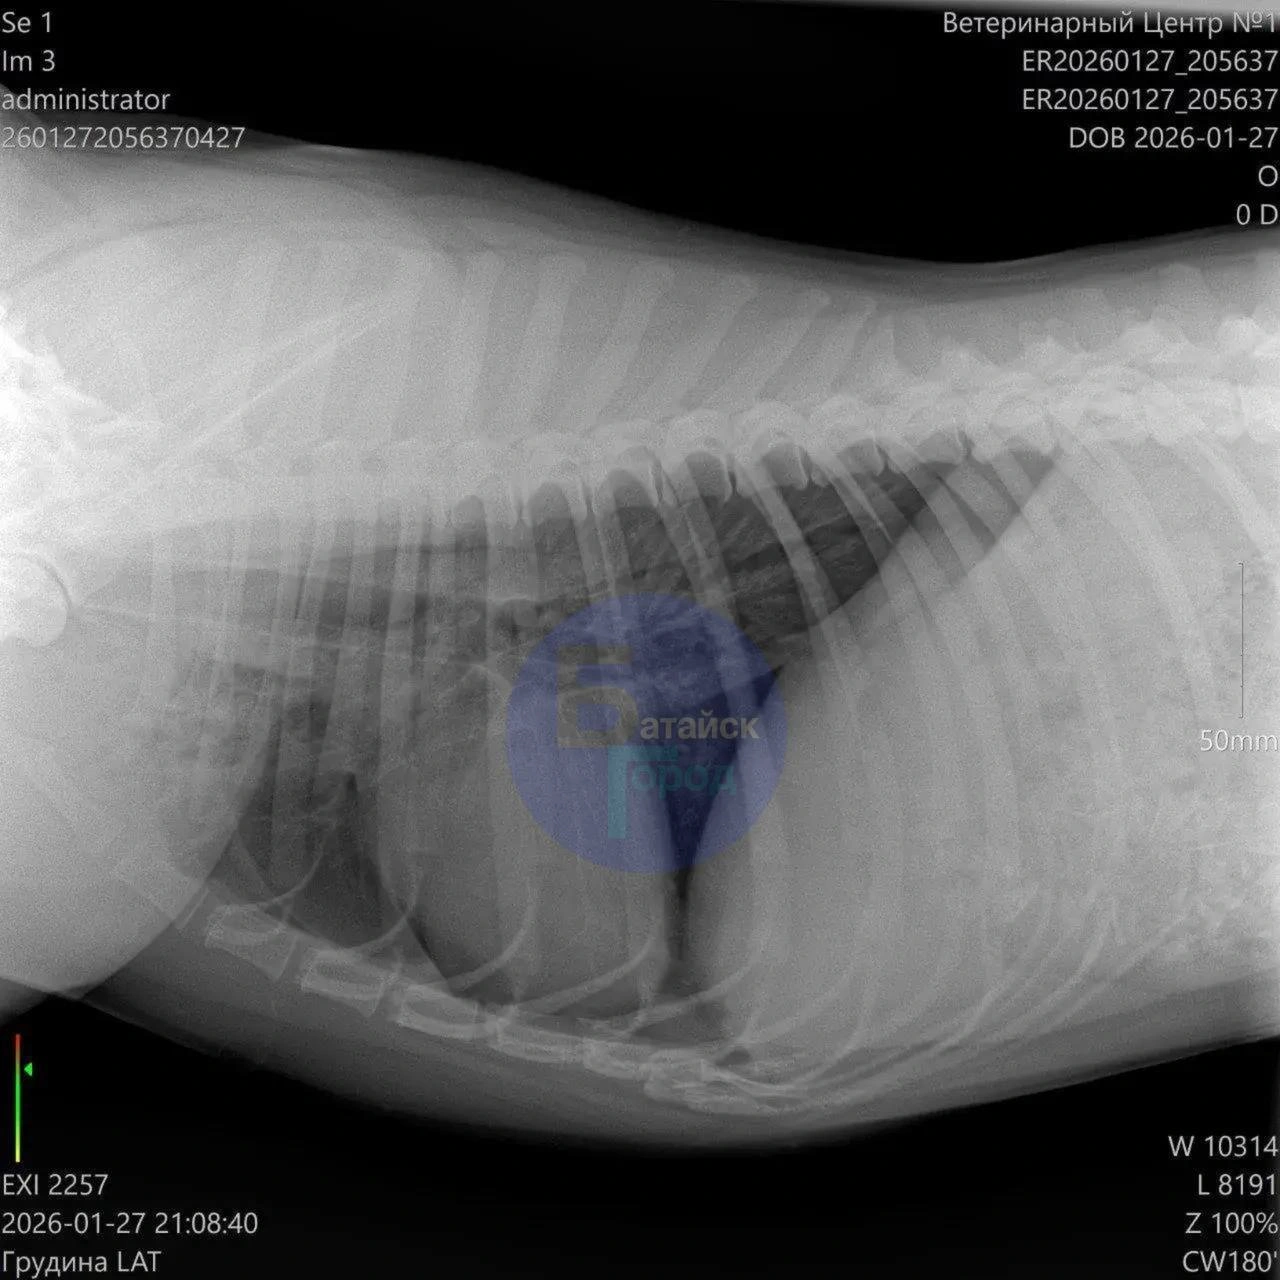

По сообщению, раненого пса обнаружили местные жители во время прогулки и отвезли в ветеринарную клинику, где животному экстренно пытались помочь. Спасти собаку не удалось — ветеринары не смогли восстановить работу сердца, пострадавшее от шока и кровопотери.